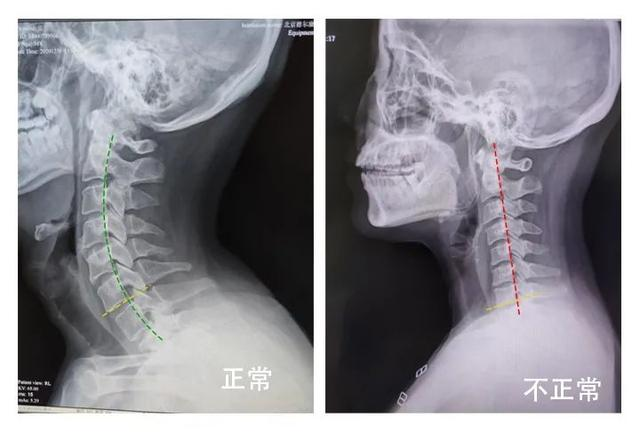

我的颈椎都直了,怎么回事?